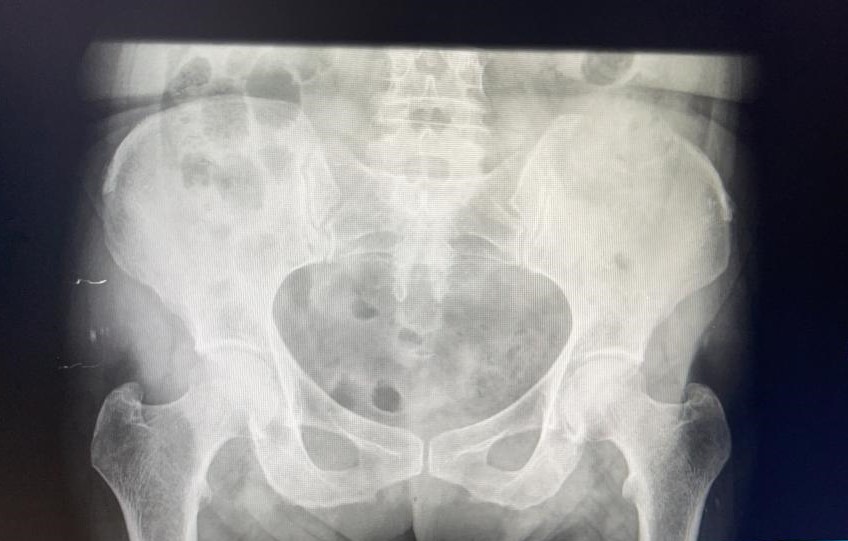

Rx pelvis: borrado de corticales en cresta ilíaca izquierda.

Se decide pedir ecografía reglada para valorar estudio posterior. Ecografía confirma sospecha de LOES intrahepáticas. Desde radiología amplian estudio con TAC: lesión ósea lítica con criterios de agresividad expansiva con masa de partes blandas en vertiente posterior de pala ilíaca izquierda.